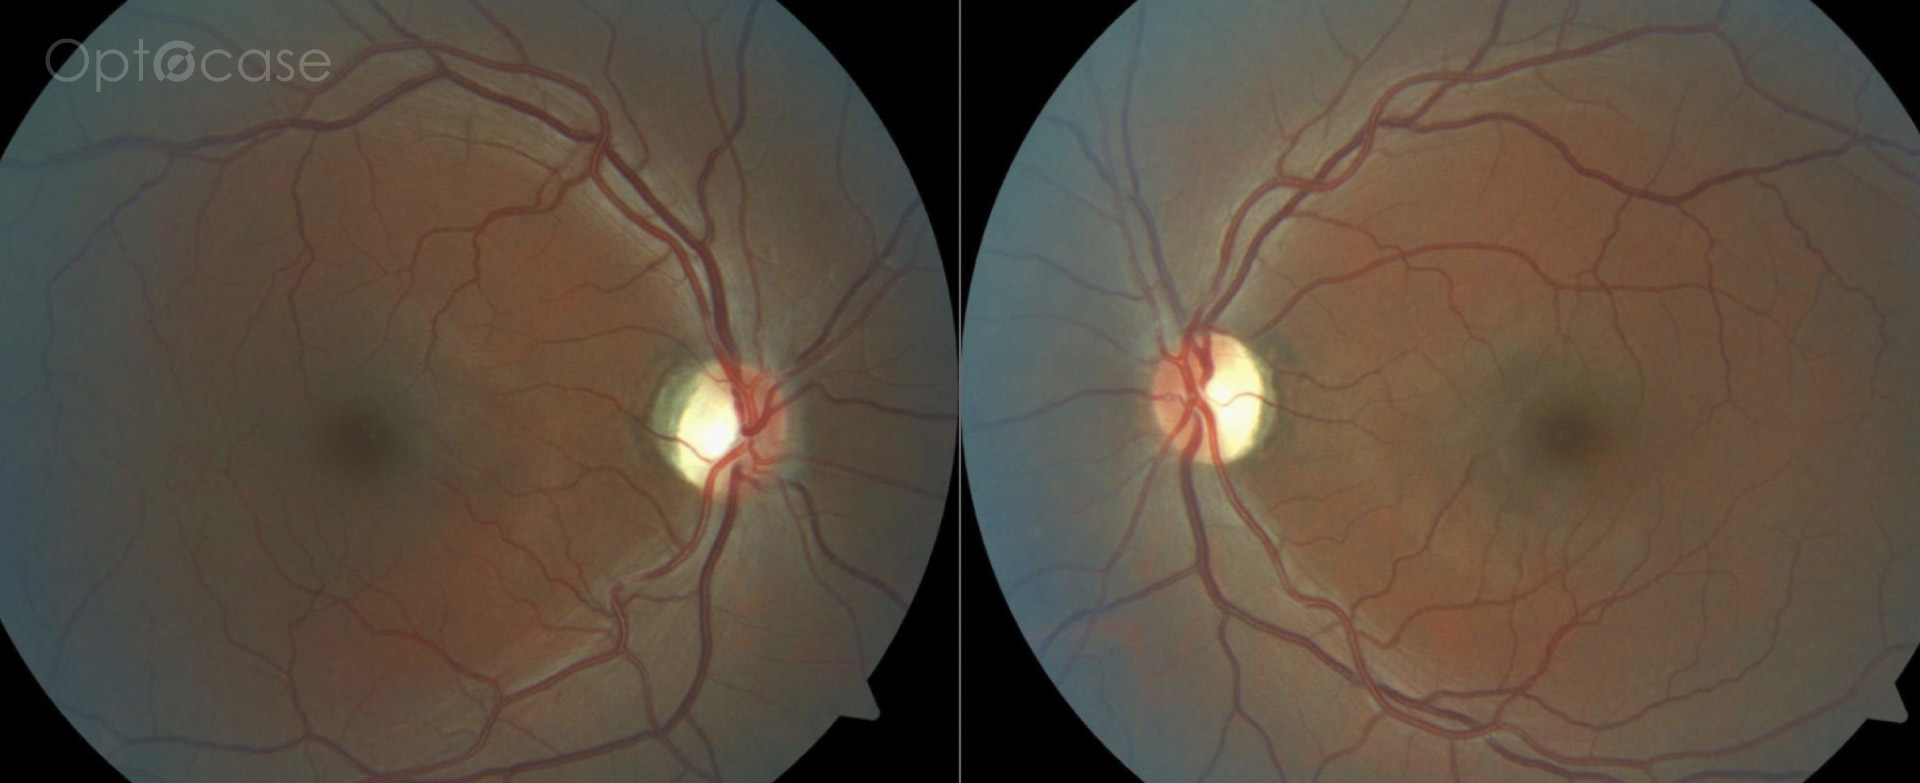

This 49 year-old patient had vertical diplopia for 2 years but normal extraocular movements. They were previously treated for a retinal condition with photodynamic therapy. Why do they have double vision?

This patient presented with vertical diplopia, normal visual acuity, no afferent pupillary defect, and full extraocular movements. He was unable to fuse Maddox rod lines with prisms except for transient fusion at distance with prisms. His OCT was normal on the right eye, but showed evidence of a past central serous retinopathy (CSR) treated with photodynamic therapy.

The patient was diagnosed with dragged-fovea diplopia syndrome.